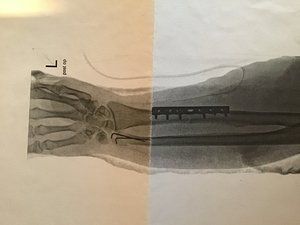

Am 12.10. habe ich mir bei einem Verkehrsunfall mit dem Fahrrad die Elle im linken Unterarm und ein Teil vom Handgelenk gebrochen.

Die Bilder sind schon sehr krass.

Also etwa 12 Wochen nach dem Unfall. Ich werde aber sicher noch einige Physiotherapie Sitzungen in Anspruch nehmen bis die Beweglichkeit wieder voll da ist.